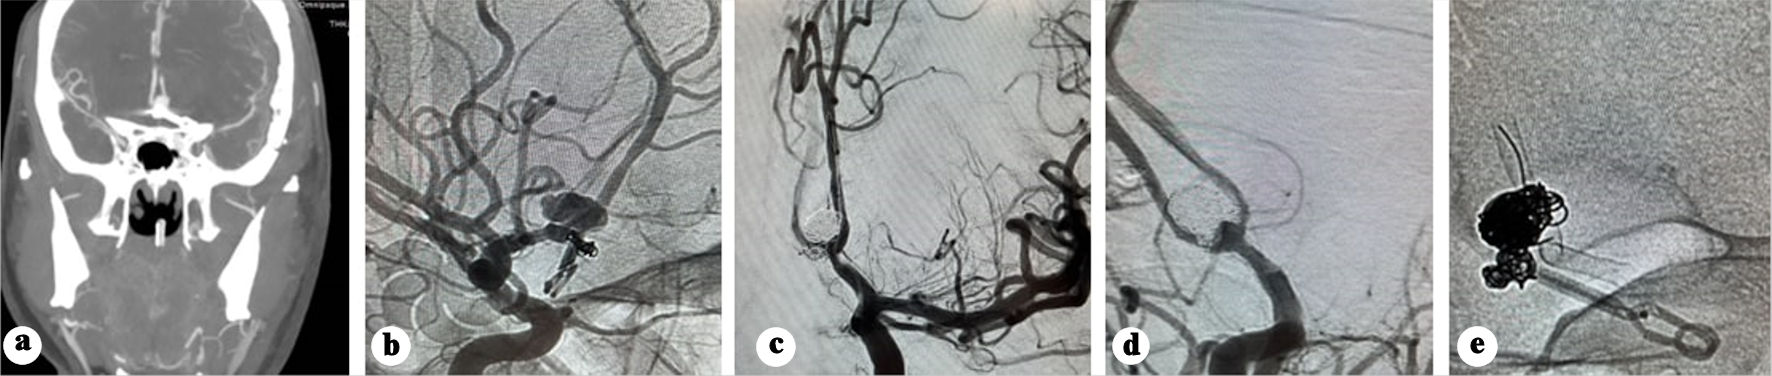

Following a 6-week hospital stay, the patient was discharged in a fully conscious state with no residual deficits. The 10-month follow-up angiography demonstrated a patent flow diverter without evidence of intimal hyperplasia and no residual aneurysm filling (Fig. 5a, b).

Figure 5. (a) Anteroposterior view of right internal carotid angiography showing no filling of the aneurysm. (b) Anteroposterior view of left internal carotid angiography showing no filling of the aneurysm.